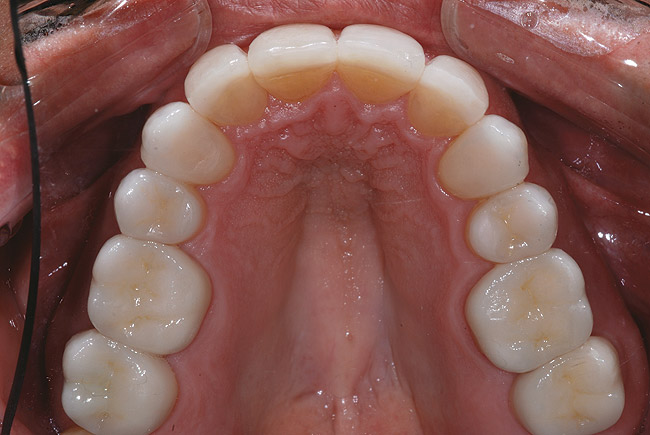

Un bărbat în vârstă de 48 ani, clinic sănătos, s-a prezentat pentru consultaţie, reclamând în principal zâmbetul său dezagreabil. Era îngrijorat cu privire la pierderea progresivă a structurii dentare pe care a constatat-o în decursul ultimilor ani şi cu privire la colorarea generalizată şi afişarea inadecvată a dinţilor şi gingiilor sale. Imaginile retractate preoperatorii relevau o formă de arcadă îngustă cu înghesuire minoră, uzură severă şi eroziune, alături de formarea unor torusuri voluminoase în regiunile maxilare vestibulare1 (fig. 1).

După finalizarea tratamentului ortodontic s-au îmbunătăţit simetria, lăţimea arcului, alinierea şi funcţia, urmând planificarea zâmbetului şi faza chirurgicală.5 Examinarea clinică după tratamentul ortodontic a evidenţiat o ocluzie long centric cu suprafeţe ocluzale plane, făcând dificilă obţinerea unei înregistrări reproductibile a ocluziei. Utilizarea unui arc facial de transfer şi înregistrarea relaţiei centrice pentru a monta anatomic modelele preoperatorii a constituit un important pas de bază. Acesta s-a realizat utilizând un deprogramator anterior simplu, care permite raportarea anatomiei şi ajută astfel la obţinerea unei înregistrări repetabile şi clare a ocluziei.6

Fotografiile finale ale acestui caz au pus în evidenţă genul de rezultate care se pot obţine urmând sistemele şi tehnicile dovedite (fig. 8-11). S-au realizat obiectivele de îmbunătăţire a raportului “alb-roz” alături de cele legate de zâmbetul pacientului. Perceperea în mod clar a obiectivelor acestui caz şi capacitatea de a comunica cu acurateţe cu pacientul şi ceramistul reprezintă o parte din cheia succesului.